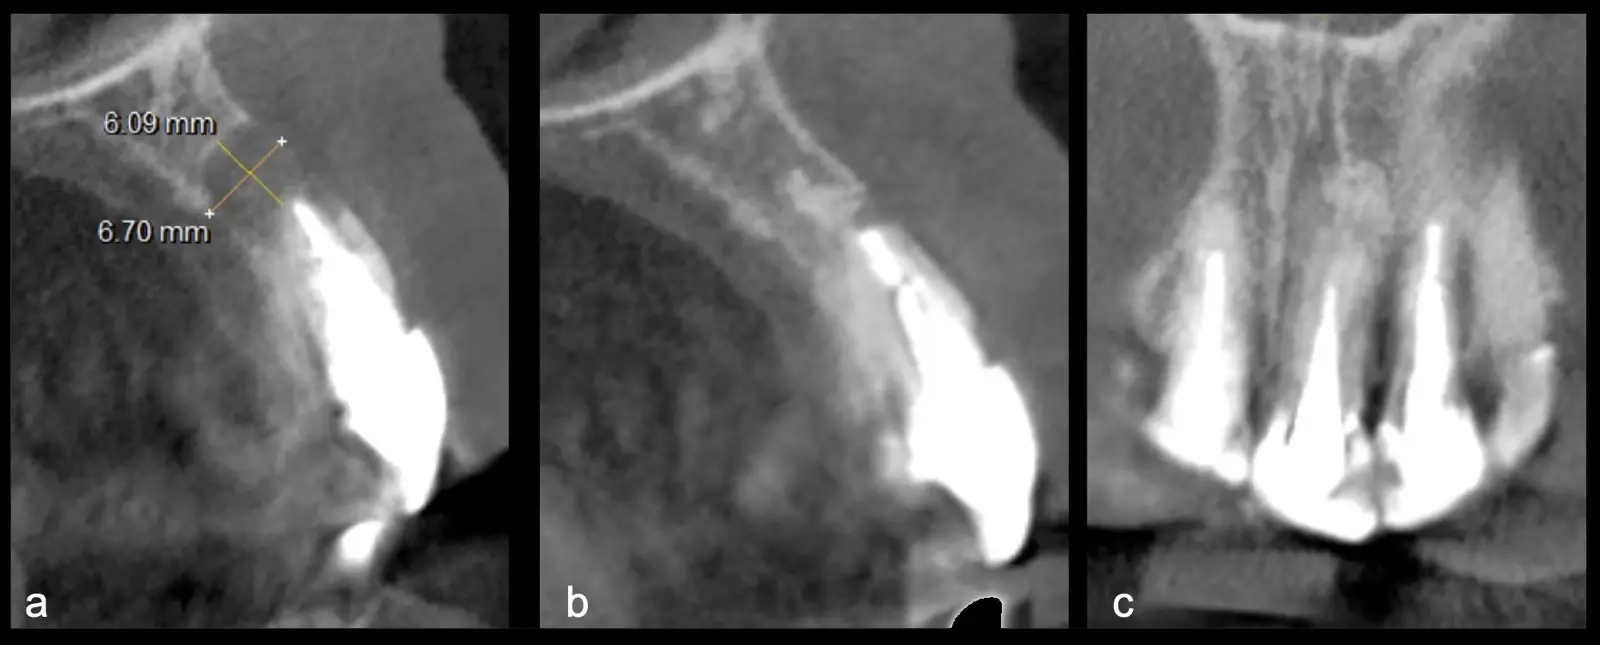

El origen puede ser bacteriano (colonias bacterianas persistentes4, patología periodontal asociada5, reinfecciones por falta de sellado coronal), mecánico (preparación deficiente, fractura de instrumentos, fracturas radiculares6, extravasación de material de obturación7 con ó sin compromiso de estructuras vecinas) y anatómico (conductos accesorios poco permeables o calcificados)8 (Figuras 1 - 4).

La microcirugía endodóntica apical busca conservar la mayor cantidad de longitud de raíz y de hueso circundante sano para no afectar la estabilidad de la pieza.11 Por ello, es ideal el uso de microscopios, elementos de magnificación, instrumental específico (insertos de ultrasonido endodónticos) y materiales de sellado eficientes para el tratamiento retrogrado. Su éxito es alto y evidencia una cicatrización ósea completa en el 74% de los casos al año de tratamiento.12 Cabe destacar que este logro está asociado también, a predictores propios de cada paciente, como la edad, tipo de pieza, profundidad de sondaje y extensión de la lesión.1 El uso complementario de la tomografía computarizada es resaltante como el instrumento imagenológico de elección para la etapa de planificación microquirúrgica,13 ya sea para una ejecución a mano alzada o con guías prefabricadas.14,15